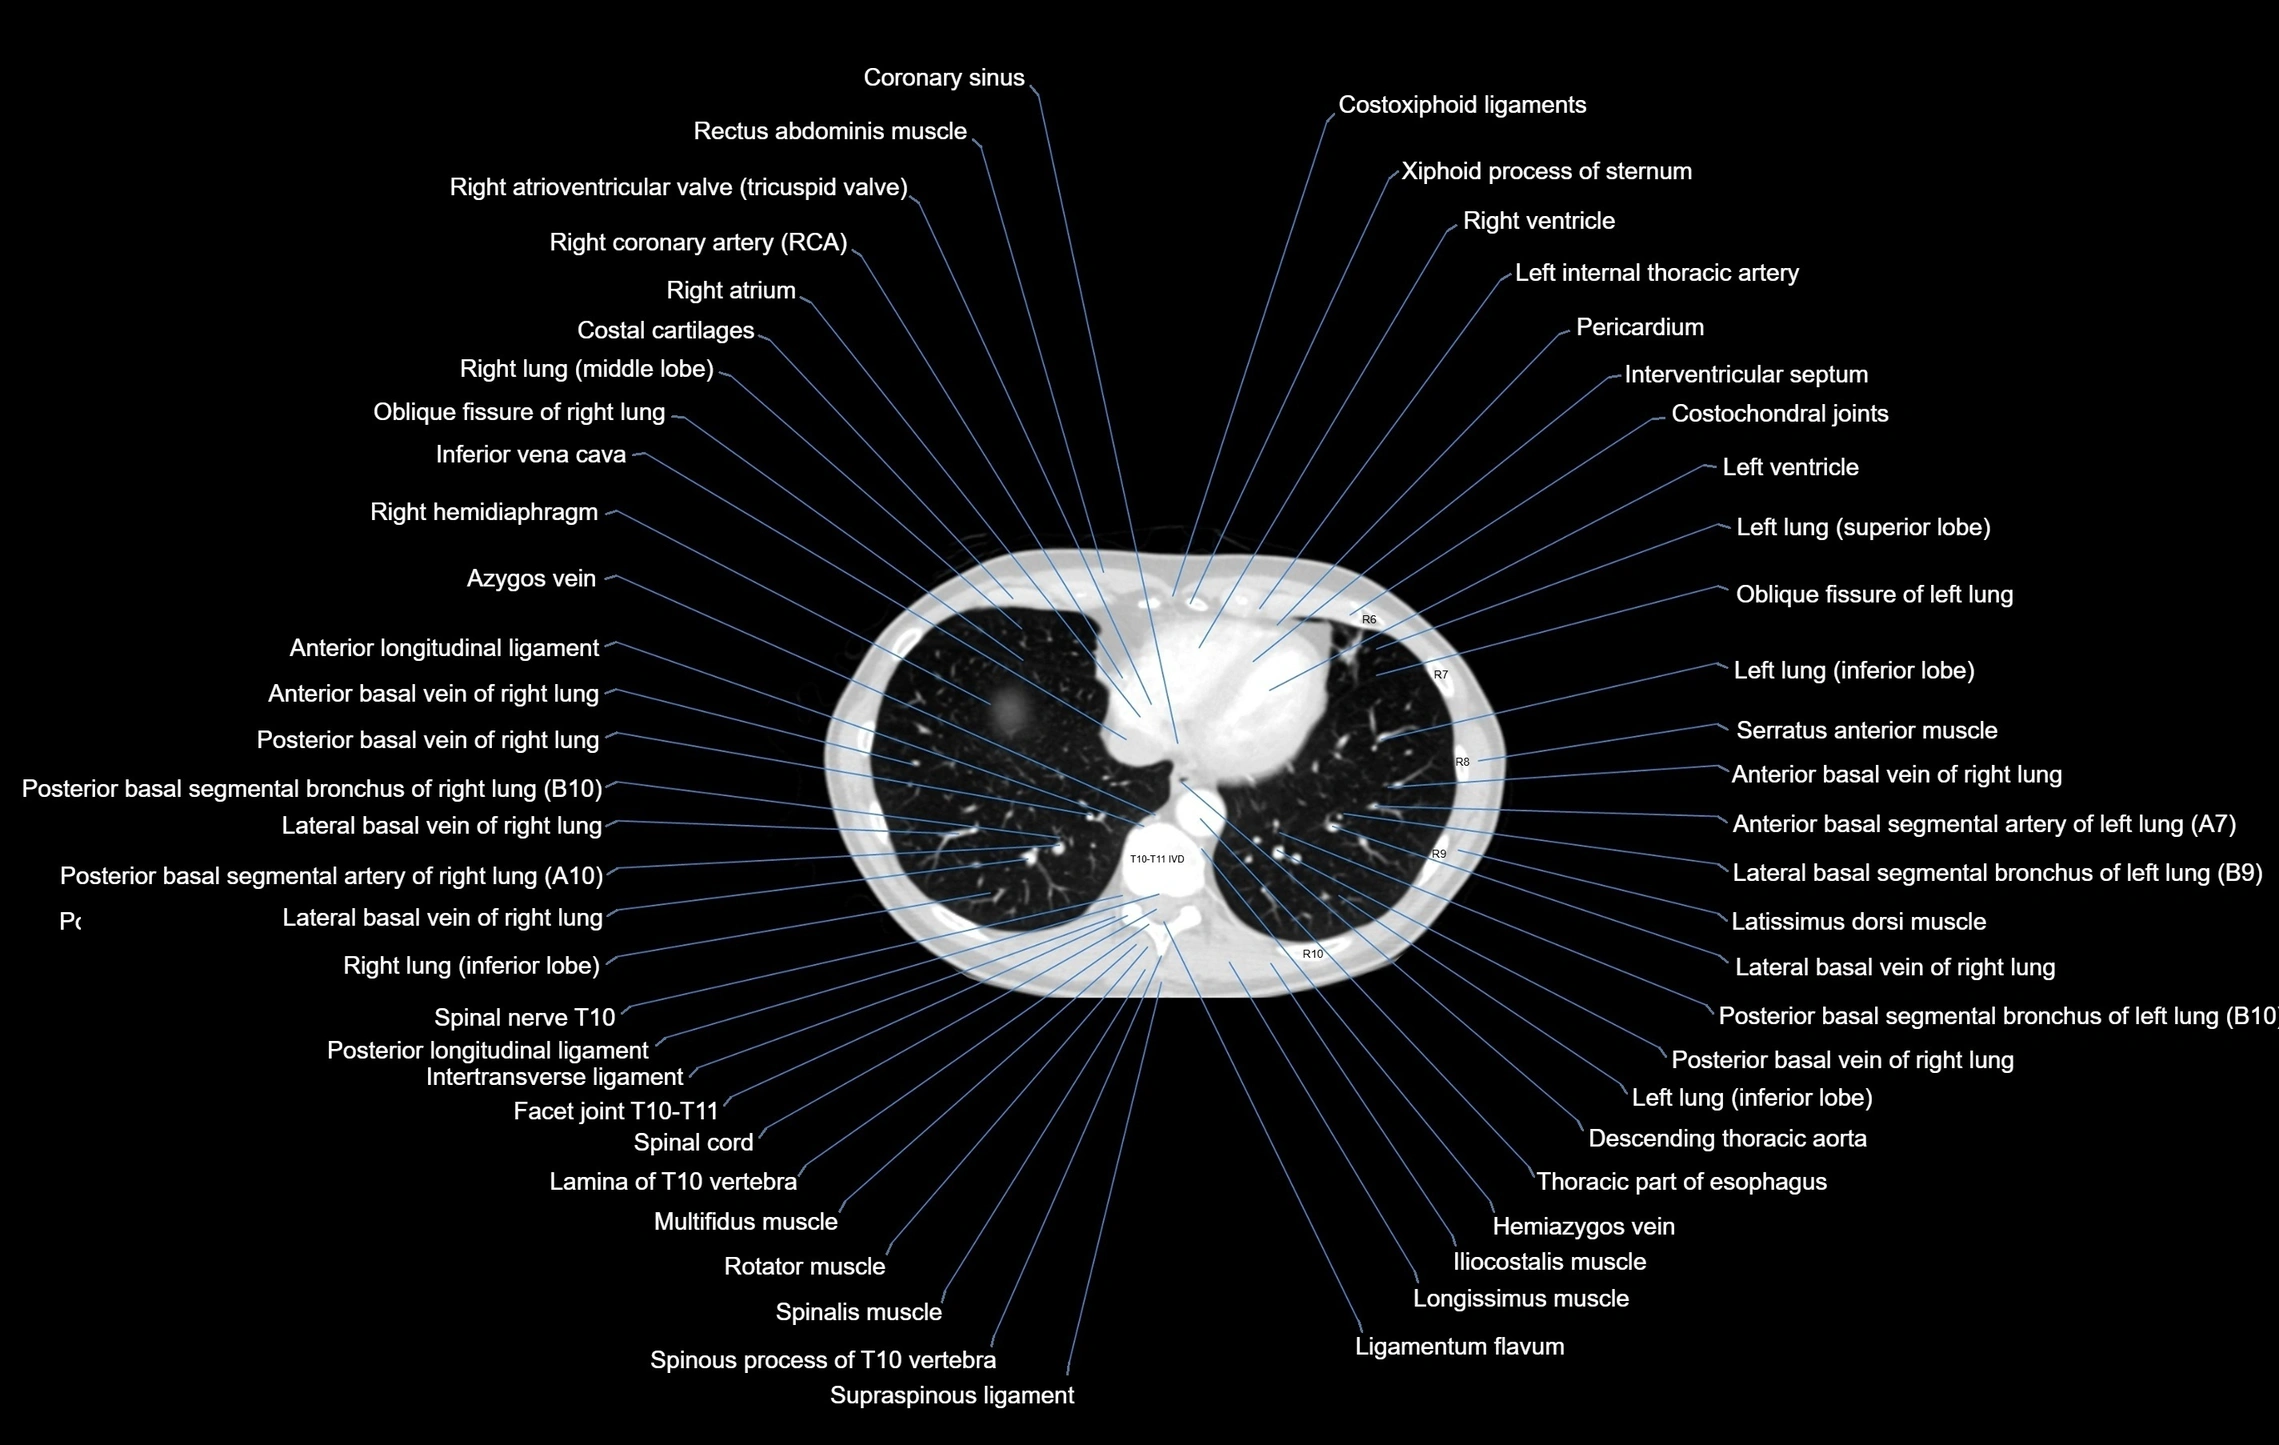

- Costal cartilages

- Costochondral joints

- Costoxiphoid ligaments

- Hemiazygos vein

- Inferior vena cava

- Interventricular Septum

- Left ventricle

- Middle lobe of right lung

- Oblique fissure of left lung

- Oblique fissure of right lung

- Pericardium

- Rectus abdominis muscle

- Right atrioventricular valve (tricuspid valve)

- Right atrium

- Right coronary artery (RCA)

- Right hemidiaphragm

- Right ventricle